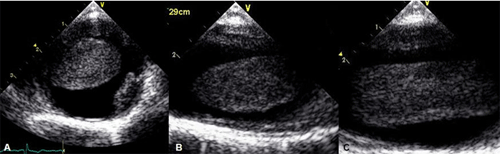

A 65 year-old man was visited out patient clinic for regular check up. Although he had a history of percutaneous coronary intervention due to old myocardial infarction 16 years ago, he had no experience of angina or other cardiovascular symptom for follow-up duration. He was a ten pack-year ex-smoker, his lipid profile was poorly controlled. The resting electrocardiogram disclosed normal sinus rhythm without any pathologic findings. The transthoracic echocardiographic examination (TTE) showed preserved systolic function and no valvular abnormality despite of old posterior wall hypokinesia. In the routine view of suprasternal notch, we found a mass-like lesion and abnormal eccentric jet in aortic arch. Subsequently, a transesophageal echocardiography (TEE) was performed for evaluation of the thoracic aorta, revealing a 3 x10 cm sized hypermobile pedunculated cylindrical mass in the aortic arch (Fig. 1). Its margin was smooth, internal contour was homogeneous comparatively. It appeared to attach to the posterior wall of the proximal aortic arch and to extend into the left subclavian artery and the descending aorta. Computer tomography confirmed the presence of the mass seen in TEE (Fig. 2). The entire thoracic aorta had normal dimensions with some visible atheromatous plaques.

¡ã Figure 1. Transesophageal echocardiographic cross-sectional (A) and longitudinal (B, C) images show a long, floating thrombus in the aortic arch. The adjacent aortic wall was thickened with diffuse atherosclerosis and focal calcified plaque.